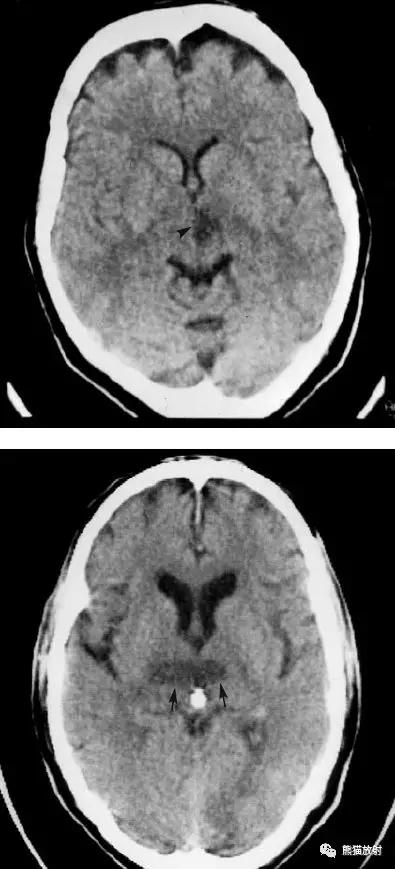

右侧大脑中动脉区域梗死的典型演变:

a)急性期

b)早期亚急性期(2天,从临床起病开始)

c)亚急性晚期(2周后)

d)慢性期(一年后)

左侧大脑中动脉血栓形成(箭头)—— “大脑中动脉高密度征”,发病后不久行CT检查:相应的血管区域见缺血性病变。